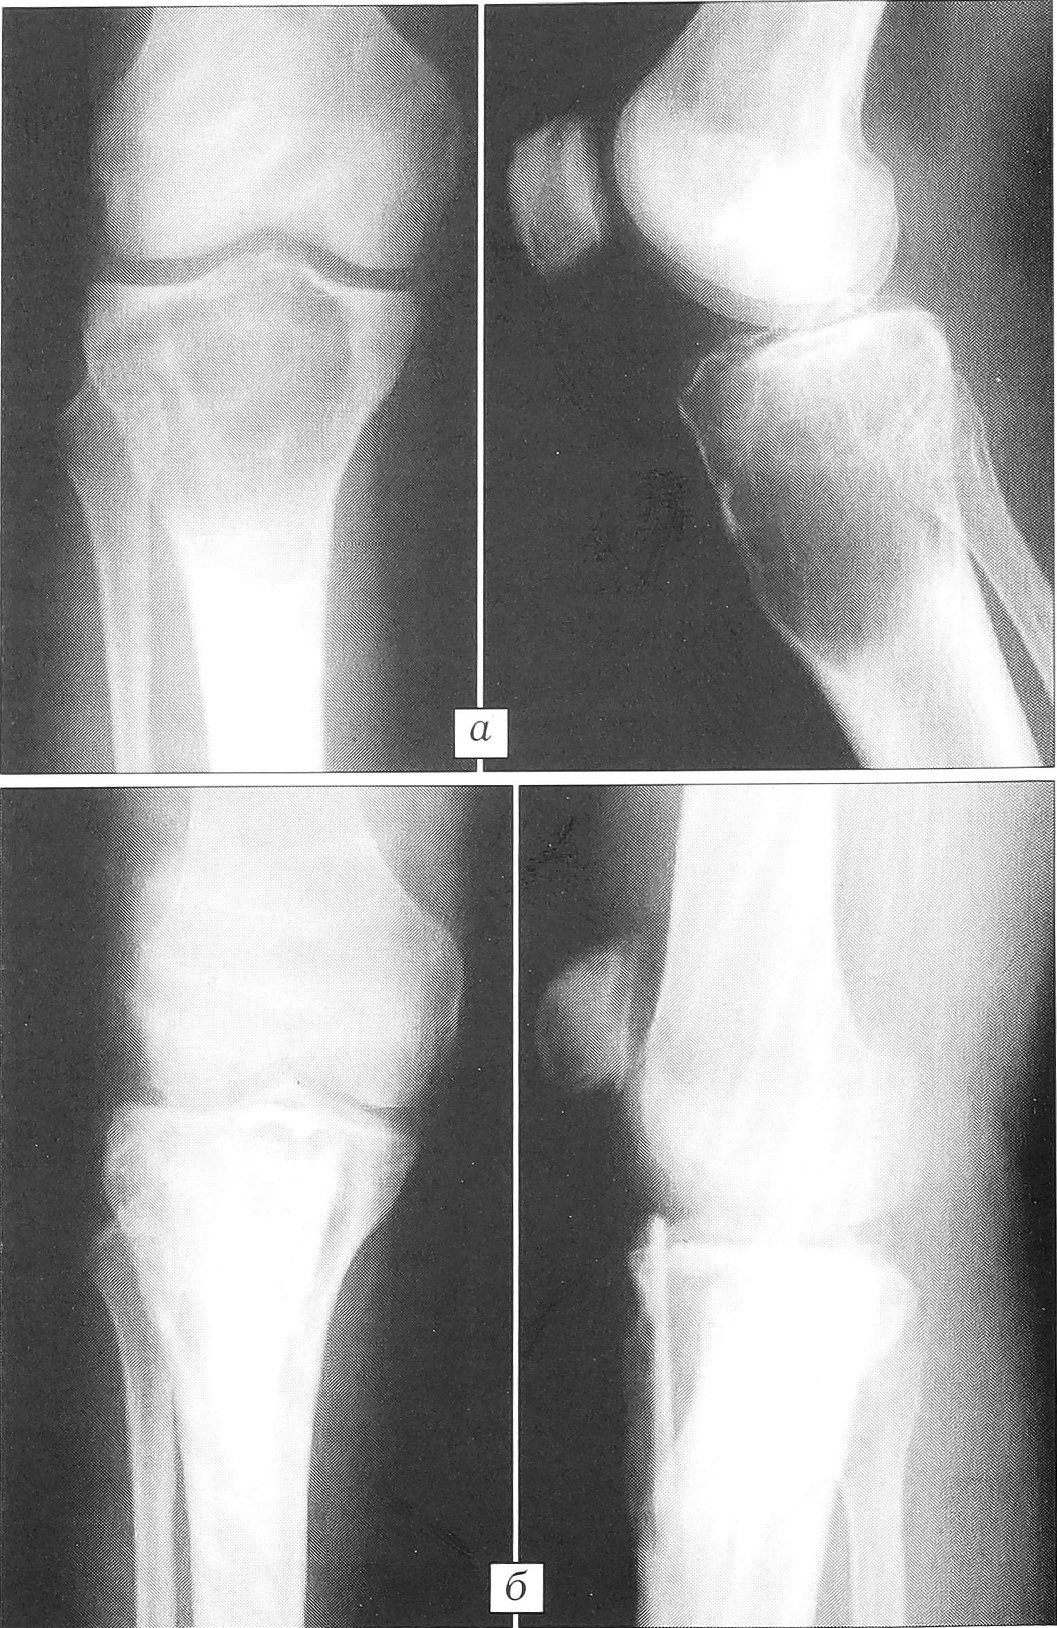

Анализ рентгенограмм показал, что через 1 мес после хирургических вмешательств картина неоднородной «глыбчатой» структуры в местах заполнения дефектов «Остеоматриксом» или в пространствах между его гранулами и аллоимплантатами, выявлявшаяся сразу после операции, полностью исчезала. Рентгеновская тень была практически однородной и имела умеренную плотность (рис. 1). Через 3 мес в большинстве случаев (66%), а через 6 мес у всех больных места, куда помещался «Остеоматрикс», по плотности рентгеновского изображения были неотличимы от окружающей губчатой костной ткани (рис. 2). Признаки перестройки замороженных кортикальных аллоимплантатов, применявшихся совместно с гранулами «Остеоматрикса», во все сроки наблюдения были минимальными (рис. 3), тогда как поверхностно-деминерализованные кортикальные аллотрансплантаты к 6-му месяцу частично инкорпорировались в материнское костное ложе (рис. 4).

Рис. 1. Рентгенограммы больной П. 24 лет. Диагноз: хондрома IV пястной кости.a — после операции с пластикой дефекта «Остеоматриксом»; б — через 1 мес.